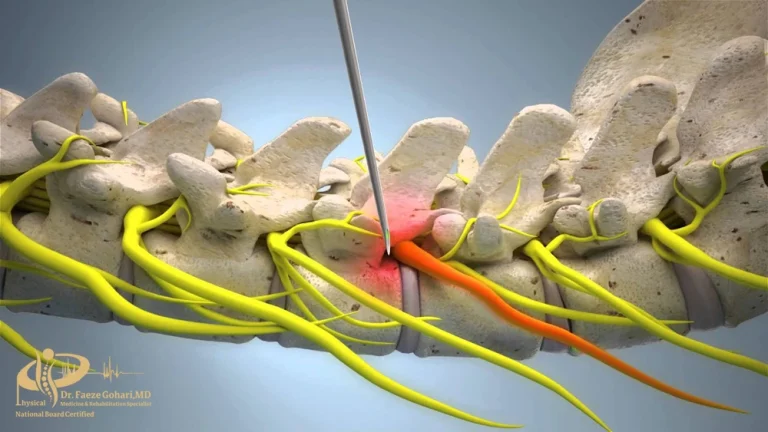

تزریق به محل عصب برای بلاک کردن مسیر انتقال پیامهای درد و علائم عصبی

عصب رشتهای از فیبرهای عصبی است که پیامهای حسی، از جمله درد، را از اندامها به نخاع و سپس مغز منتقل میکند و در واقع مسیر اصلی انتقال احساس درد به شمار میرود. در بلوک عصبی، پزشک با استفاده از یک سوزن باریک و تحت هدایت تصویربرداری دقیق، داروهایی مانند بیحسی، ضدالتهابی یا ترکیبی از هر دو را در اطراف عصب تزریق میکند. این داروها انتقال پیام عصبی را به طور موقت مختل میکنند و در نتیجه سیگنال درد به مغز نمیرسد.

نحوه انجام بلوک عصبی ستونفقرات

- بلوک با تزریق دارو

در این روش، پزشک با کمک تصویربرداری (فلوروسکوپی) سوزن ظریف را در کنار عصب یا مفصل موردنظر قرار میدهد و داروهایی مانند بیحسی موضعی یا کورتون تزریق میکند. این داروها التهاب را کاهش میدهند و انتقال پیامهای درد را بهطور موقت متوقف میسازند. این روش معمولاً با بیحسی موضعی انجام میشود و بهجز سوزش مختصر یا فشار خفیف هنگام ورود سوزن و تزریق دارو، درد قابل توجهی ندارد. خود تزریق معمولاً ۱۵ تا ۳۰ دقیقه طول میکشد و اثر آن از چند روز تا چند ماه باقی میماند.